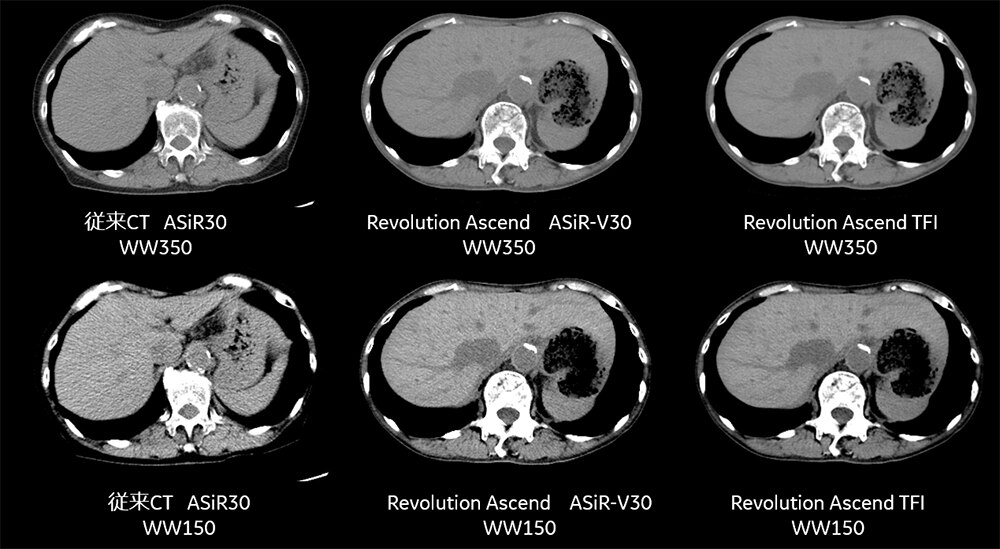

るい瘦患者様では脂肪が少なく、腹水などを有している場合には特にコントラストがつかないため通常の画像では読影困難な印象がありますが、Auto Prescriptionによって自動的にNIが通常のNIより低くなることでSDが向上し、WWを狭めてコントラストをつけても画質が十分に担保されます。

従来CTでは通常NI9.8で撮影しており小さい患者様にも同様のNIのため、コントラストをあげるためにWWを150に絞るとノイジーに感じられますが、Ascendでは通常NIに対しAuto Prescriptionによって自動的にNIが調整されWWを絞ってもノイズの少ない良好な画像を得ることができています。また、TFIを用いることでさらなるノイズの少ない良好な画像を得ることができています。(Fig8)

Fig8. 従来CTとRevolution Ascendでの体格が小さい方での腹部画像の比較